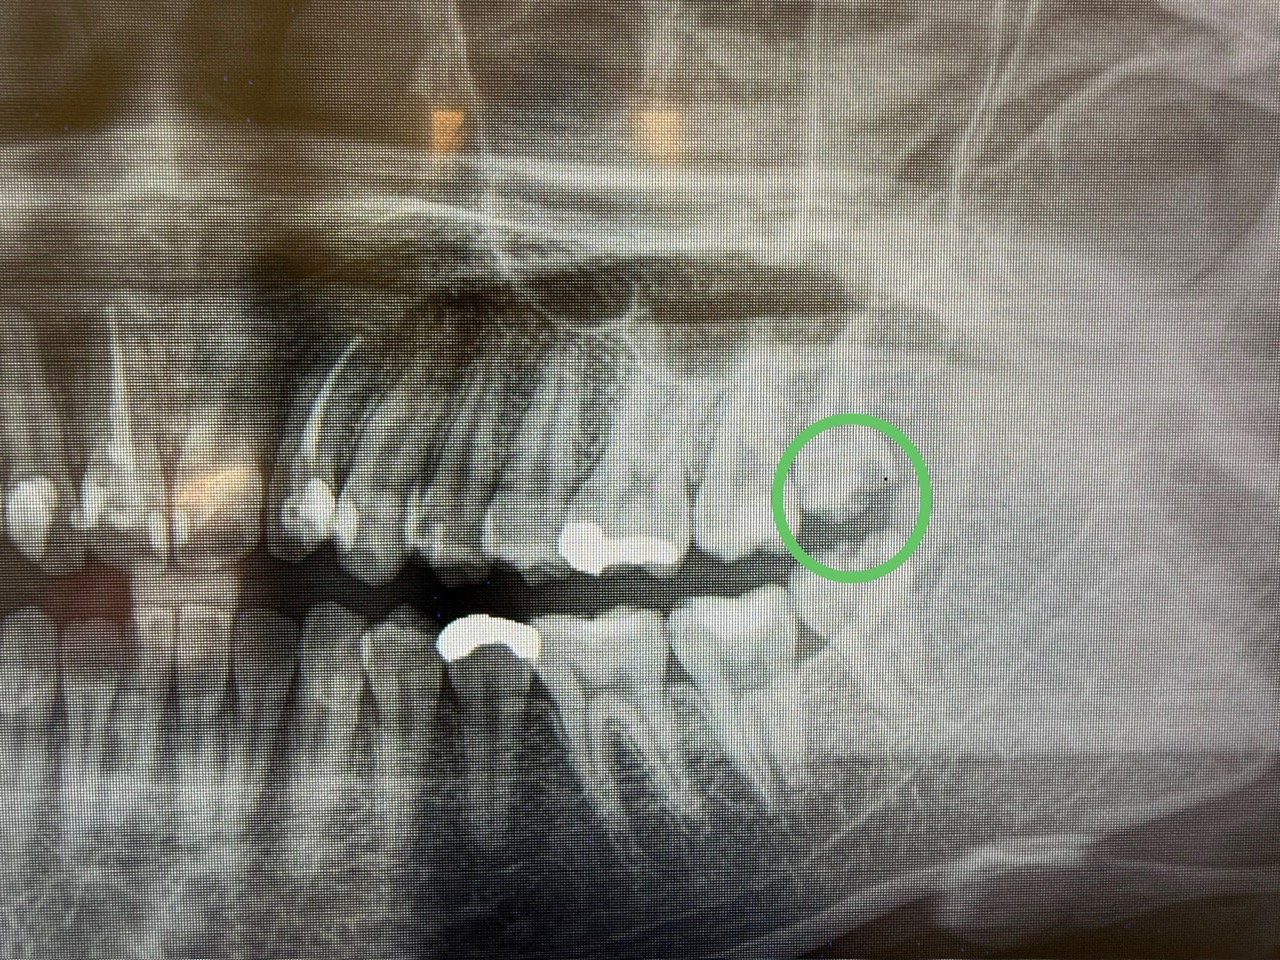

抜歯をしたあと、隣の歯をチェック!

やっぱりむし歯になっていました。